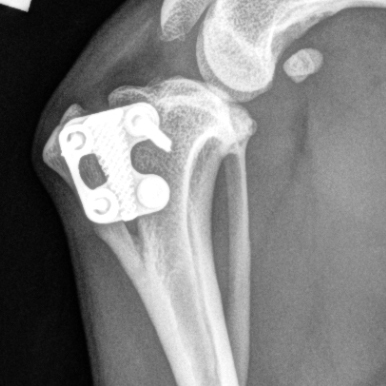

The RITA LEIBINGER Titanium TTA RAPID® Tiny, 2.0/2.4 TPLO and Titanium TPLO Swing, and our 2.0/2.4 Titanium CBLO implant systems and instrumentation are specifically designed for small patients, and can help overcome these challenges. They are typically smaller in size and have different geometries to accommodate the smaller bone structure of small dogs and cats.